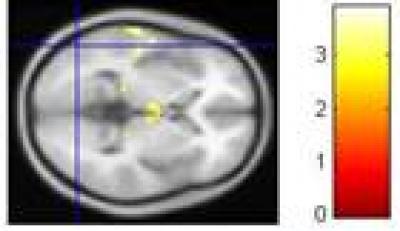

A recent study published in the Neural Regeneration Research (Vol. 8, No. 18, 2013) combined cognition tasks and functional MRI, and designed multiple repeated event-related tasks; additionally, using the International Affective Picture System-based event-related tasks, this study investigated brain functional characteristics of major depressive disorder patients exhibiting, negative bias brain imaging changes and cognitive dysfunction, as well as their relationship based on biased quantitative data. Results show that (1) the number of error responses was calculated to identify bias of emotion recognition between patients with major depressive disorder and normal controls, suggesting that the depressed patients exhibited negative bias towards emotion task stimuli based on quantitative data; (2) the activation of the occipital lobe was attenuated in depressed patients when doing emotion tasks; (3) Deficits in the occipital lobes may be an initiating factor for depression onset, which results in attention deficit disorder and cognitive dysfunction.

Functional MRI showed that the activation of some regions in the frontal lobe, temporal lobe, parietal lobe, limbic lobe was enhanced when the patients were watching negative pictures compared with normal controls.